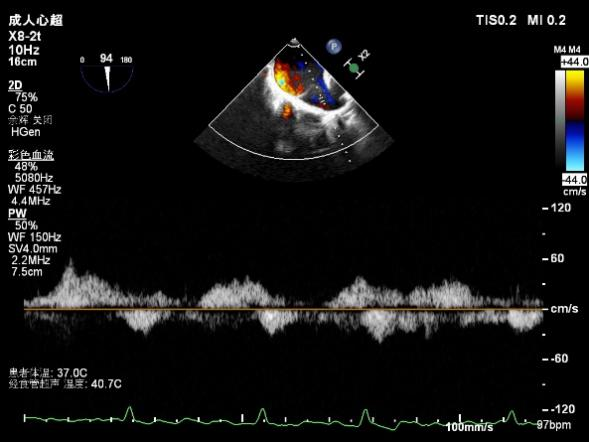

3D-color MV view:源自于交界区的大量反流

Qlab软件勾画估测瓣口面积约:6.52cm²